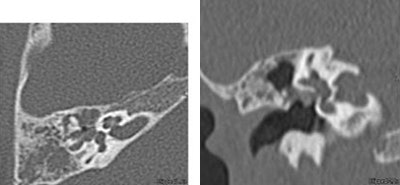

For sinus disease, Greenberg's group favors thin sections in a single plane (1-mm collimation, 80 kVp, 200 mAs) viewed on coronal reconstructions.

| Axial (left) and coronal (right) images of a 3-year-old with right maxillary sinus disease. Axial 1-mm thick sections were acquired at 80 kVp and 200 mAs, and viewed using coronal reconstructions. |